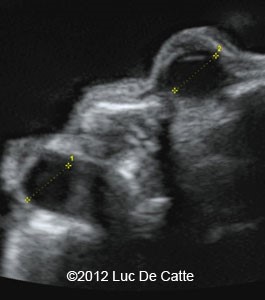

Hypotelorism & Hyperrelorism

HYPOTELORISM

Ass with: holorprosencephaly, microcephaly, chromosomal abnormalities

HYPERRELORISM

Ass with: encephalocele, facial cleft/cleft lip, megalencephaly, agenesis of corpus callosum.